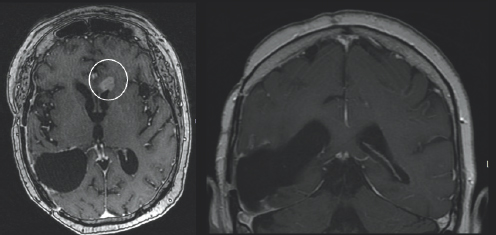

One can also imagine why she would ask herself such a painstaking question, “Why me?”, when she received a (GBM) diagnosis at the age of 66. Janet noted an intense thirst and painful, persistent urination in May of 2017. These symptoms prompted her to visit her primary care physician. Suspicious Janet might have of an overactive bladder or diabetes insipidus, which is characterized by chronic thirst and urination due to an imbalance of fluids within the body, her physician sent her in for imaging. On June 24th, 2017, however, her life would change forever. Janet’s imaging showed a right posterior temporal brain lesion that indicated the existence of a GBM (Fig. 3.1). This location falls on the right side of the head, in the back portion of the brain, synonymous with the location behind the ear. She thought, “I had [cancer] once, I shouldn’t have it again”. She later underwent extensive surgery to resect the tumor. The tumor was analyzed by pathologists at Emory, who shared it was O[6]-methylguanine-DNA methyltransferase (MGMT) methylated, epidermal growth factor receptor (EGFR) viii amplified, and isocitrate dehydrogenase 1 wild type (IDH-1 WT).

Variations of gray color are surrounded by a both a black and light gray boarder. On the left side of the image, there is a white blob outline.

FIGURE 3.1 Brain MRI before surgery. Axial (left) and coronal (right) post-contrast images show a large mass centered in the right posterior temporal lobe with peripheral and irregular enhancement that appears bright after being injected with IV contrast, consistent with glioblastoma.